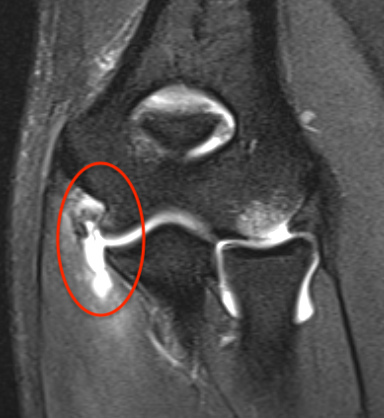

Acute full thickness UCL tear

UCLUCL